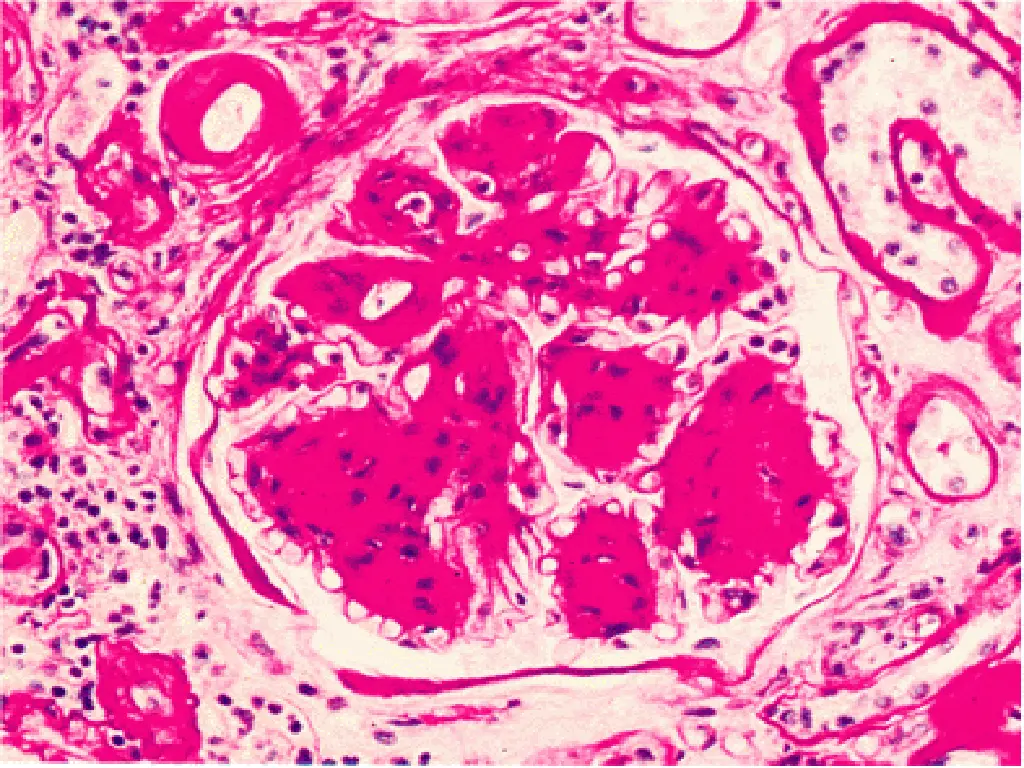

Complications of Diabetes Diabetic Microvascular Disease: - Responsible for Many of the Complications of Diabetes, Including Renal Failure and Blindness - Arteriolosclerosis and capillary basement membrane thickening are characteristic vascular changes in diabetes. - The frequent occurrence of hypertension contributes to the development of the arteriolar lesions. In addition, deposition of basement membrane proteins, which may also become glycosylated, increases in diabetes. - Aggregation of platelets in smaller blood vessels and impaired fibrinolytic mechanisms have also been suggested as playing a role in the pathogenesis of diabetic microvascular disease.

Complications of Diabetes Diabetic Microvascular Disease: - The effects of microvascular disease on tissue perfusion and wound healing are profound - Reduce blood flow to the heart, which is already compromised by coronary atherosclerosis. - Healing of chronic ulcers that develop from trauma and infection of the feet in diabetic patients is commonly defective

Diabetic Nephropathy - 30% to 40% of T1DM ultimately develop renal failure. A somewhat smaller proportion (up to 20%) of patients with T2DM are similarly affected - Diabetic nephropathy accounts for one third of all new cases of renal failure. - The prevalence of diabetic nephropathy increases with the severity and duration of the hyperglycemia. - Kidney disease due to diabetes is the most common reason for renal transplantation in adults. - The glomeruli in the diabetic kidney exhibit a unique lesion termed Kimmelstiel-Wilson disease or nodular glomerulosclerosis